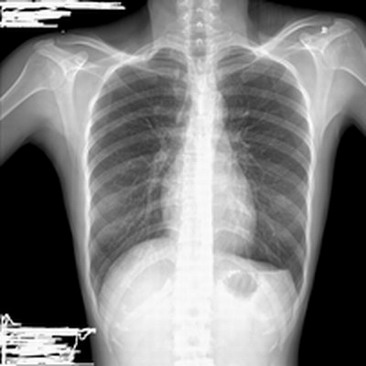

女 25岁 体检发现左下胸液平面

左下胸存在液平是肯定的

因为我们在透视下观察过,可以见到随着呼吸跳动的液平

建议立、卧位结合多轴位透视,若确定是液气平面则考虑包裹性(或部分包裹性)液气胸。仅凭上幅照片,很像胸膜粘连。(透视的优点常不被重视,ct的缺点很容易被忽略?)

如果是透视下可动的话那应该是肺囊肿了

如果透视下见液平,,,那当是液气囊肿,绝不是胸腔积液了!!!!

目前无任何症状考虑肺囊肿可能。请详细询问病史并结合进一步检查诊断

楼主已经进行了透视,液平面可能是存在的,胸膜粘连肯定是除外了,肺空腔性病变(大泡、肺囊肿等)应该是除外了,不会是横隔反转吧?